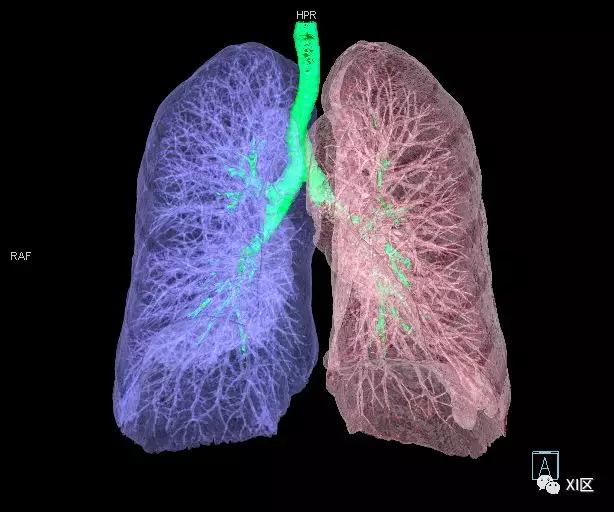

气管支气管树与两肺融合显示

气管树与左右肺的关系